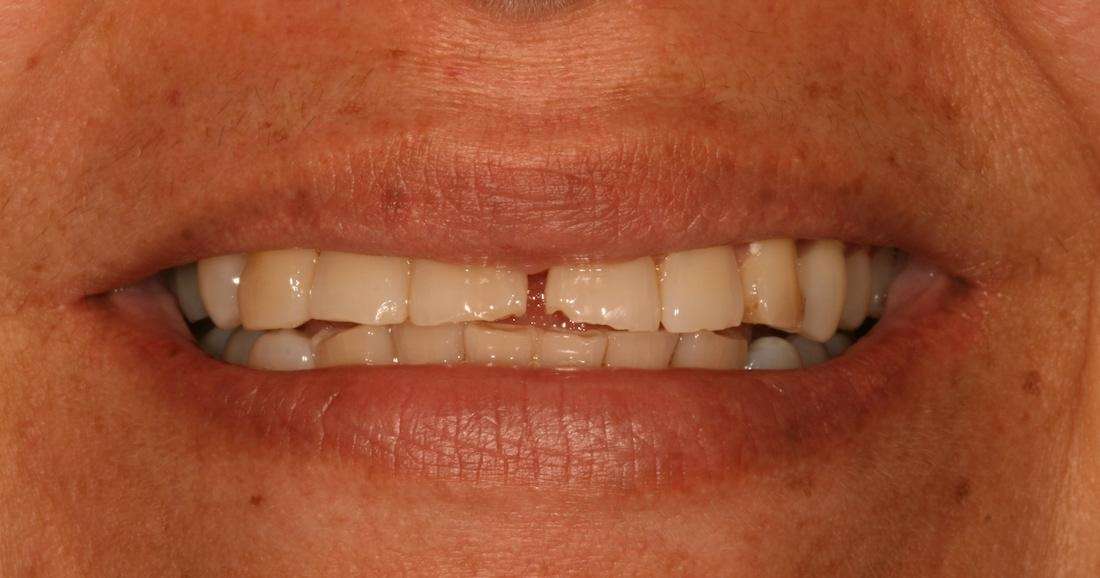

A full smile make-over has been life changing for RP. She only wishes she had done it sooner!

Before

After